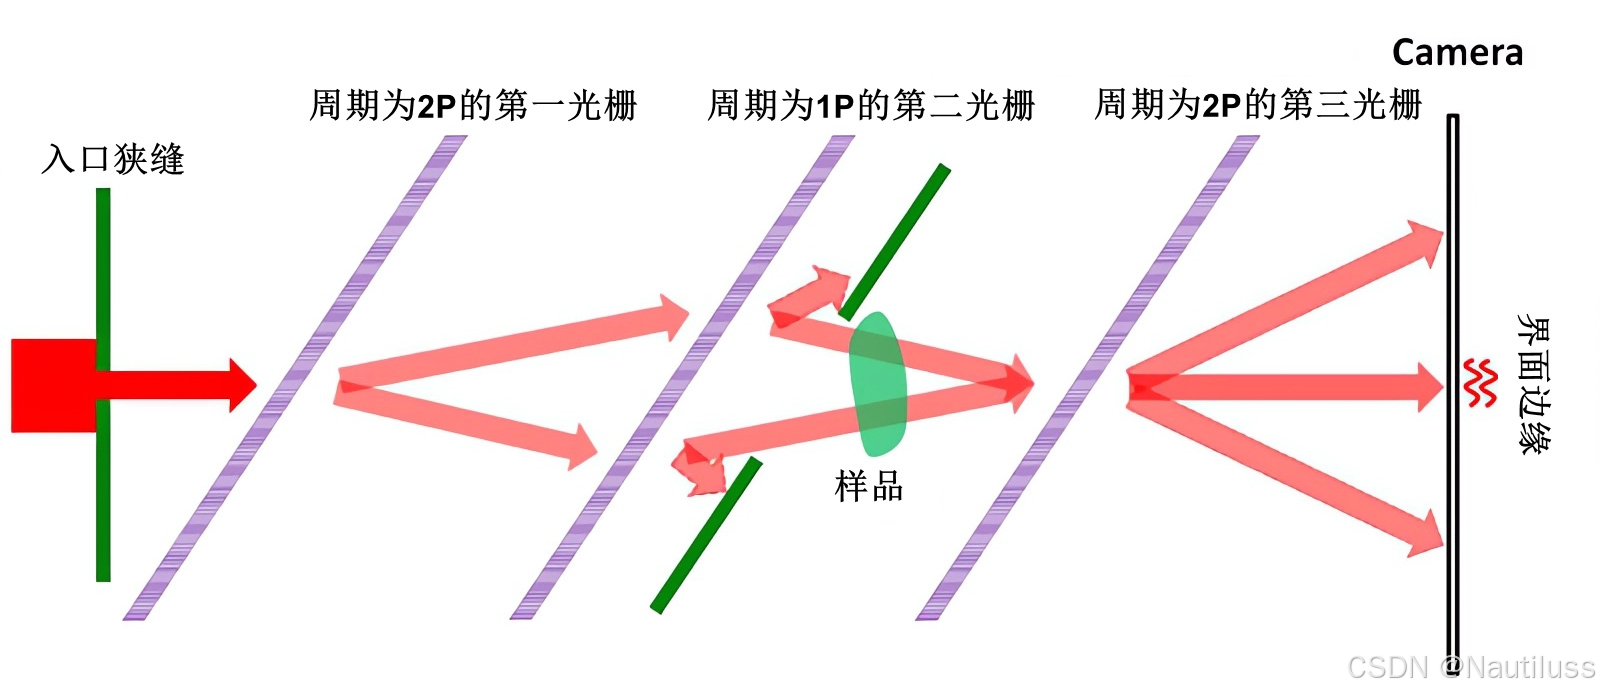

2、纳米X射线相移光栅干涉测量

为了获得晶体 Bonse-Hart 干涉测量的卓越灵敏度,同时避免一些基本限制,单片晶体已被纳米 X 射线相移光栅取代。它可以在普通 X 射线管的宽能谱范围内分裂 X 射线束。在光栅Bonse-Hart干涉法中,周期性光栅被引入X射线的路径中,这些光栅与X射线发生相互作用,产生干涉图样,可用于从X射线束中提取相位信息。

2、基于光栅的成像(GBI)

在光栅干涉仪中,第一个光栅 (G1 )将入射光束分成两个一级衍射。这两束光束在第一个光栅的下游衍射,相互干涉,并形成线性周期性条纹图案。相位物体的存在会引起条纹的位移。与条纹具有相同周期性和方向的第二个光栅(G2 )直接插入到探测器前面,以读取条纹并获得物体的折射。因此,可以从G2检测器上的步进读数恢复条纹。为了利用 G2将相位调制转换为强度调制,根据塔尔博特效应计算第一和第二光栅之间的距离。因此,这种方法也被称为“塔尔伯特干涉仪”。

然而,该方法还需要高度相干和高亮度的X射线源,限制了其在实验室源和商业用途中的应用。2006 年,Pfeiffer 等人。在该方法中引入了另一个光栅,因为该光栅紧邻 X 射线源放置。这个光栅创建了一系列单独相干但相互不相干的光源。由于 Lau 效应 ,这些光源的 Talbot 效应在 G2平面上相互重叠,使得该方法适用于非相干和低亮度光源。新引入的X射线光栅干涉仪也被称为“Talbot-Lau干涉仪”。使用 Talbot-Lau 干涉仪时,实验装置中的仪器校准相对简单,可实现大视场。该方法正在成为生物样品最流行的 X 射线相衬图像之一。

医院使用的X射线没有均匀的波,因此不能直接使用塔尔博特效应。通过在 X 射线源附近放置一个额外的网格解决了这个问题。新添加的光栅旨在仅将对齐的 X 射线传递到下游塔尔博特干涉仪。通过这一创新,它将Talbot干涉仪的成像原理应用到已在医院使用的X射线源上,并显着缩短了成像时间。